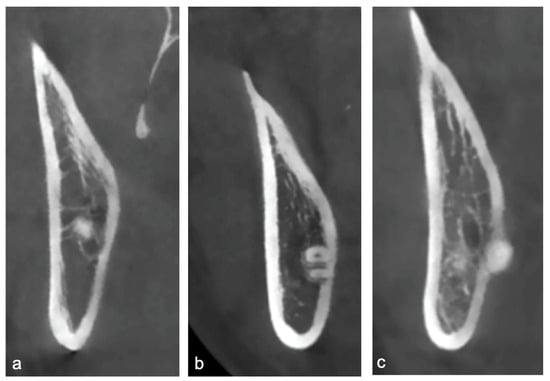

- Root Apex Position: The topographic relationship between the root apex and the lingual plate was categorized as non-contact, contact, or perforating (Figure 2). The presence or absence of lingual cortical perforation was assessed at three anatomical levels of each impacted mandibular third molar: the cementoenamel junction (CEJ), mid-root, and root apex.